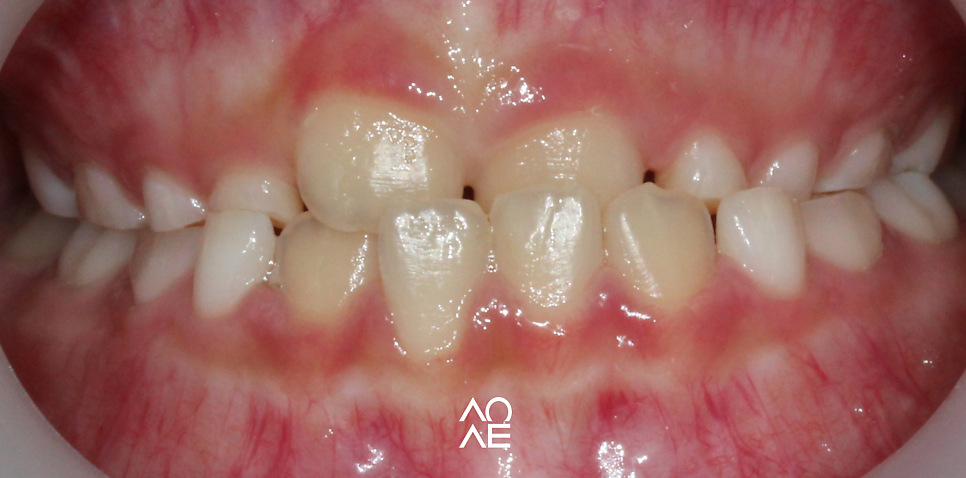

주걱턱 부정교합

생각보다 주변에 주걱턱 부정교합을

가지고 있는 친구들이 많이 있는데요

주걱턱 부정교합은

상악의 성장이 부족하거나

하악의 성장이 과도하거나

이런 사유로 상악의 앞니가 하악 앞니보다

돌출된 경우를 주로 이야기 합니다